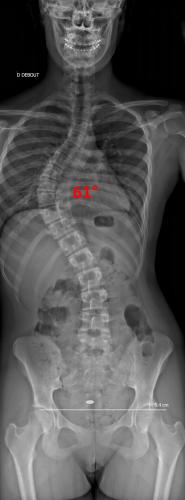

Images de scolioses opérées 16 janvier 202418 janvier 2023 par Damien Scoliose Thoracique 1 Radiographie pré-opératoire de Face Radiographie pré-opératoire de Profil Radiographie de Face à 3 mois post-opératoire Radiographie de Profil à 3 mois post-opératoire